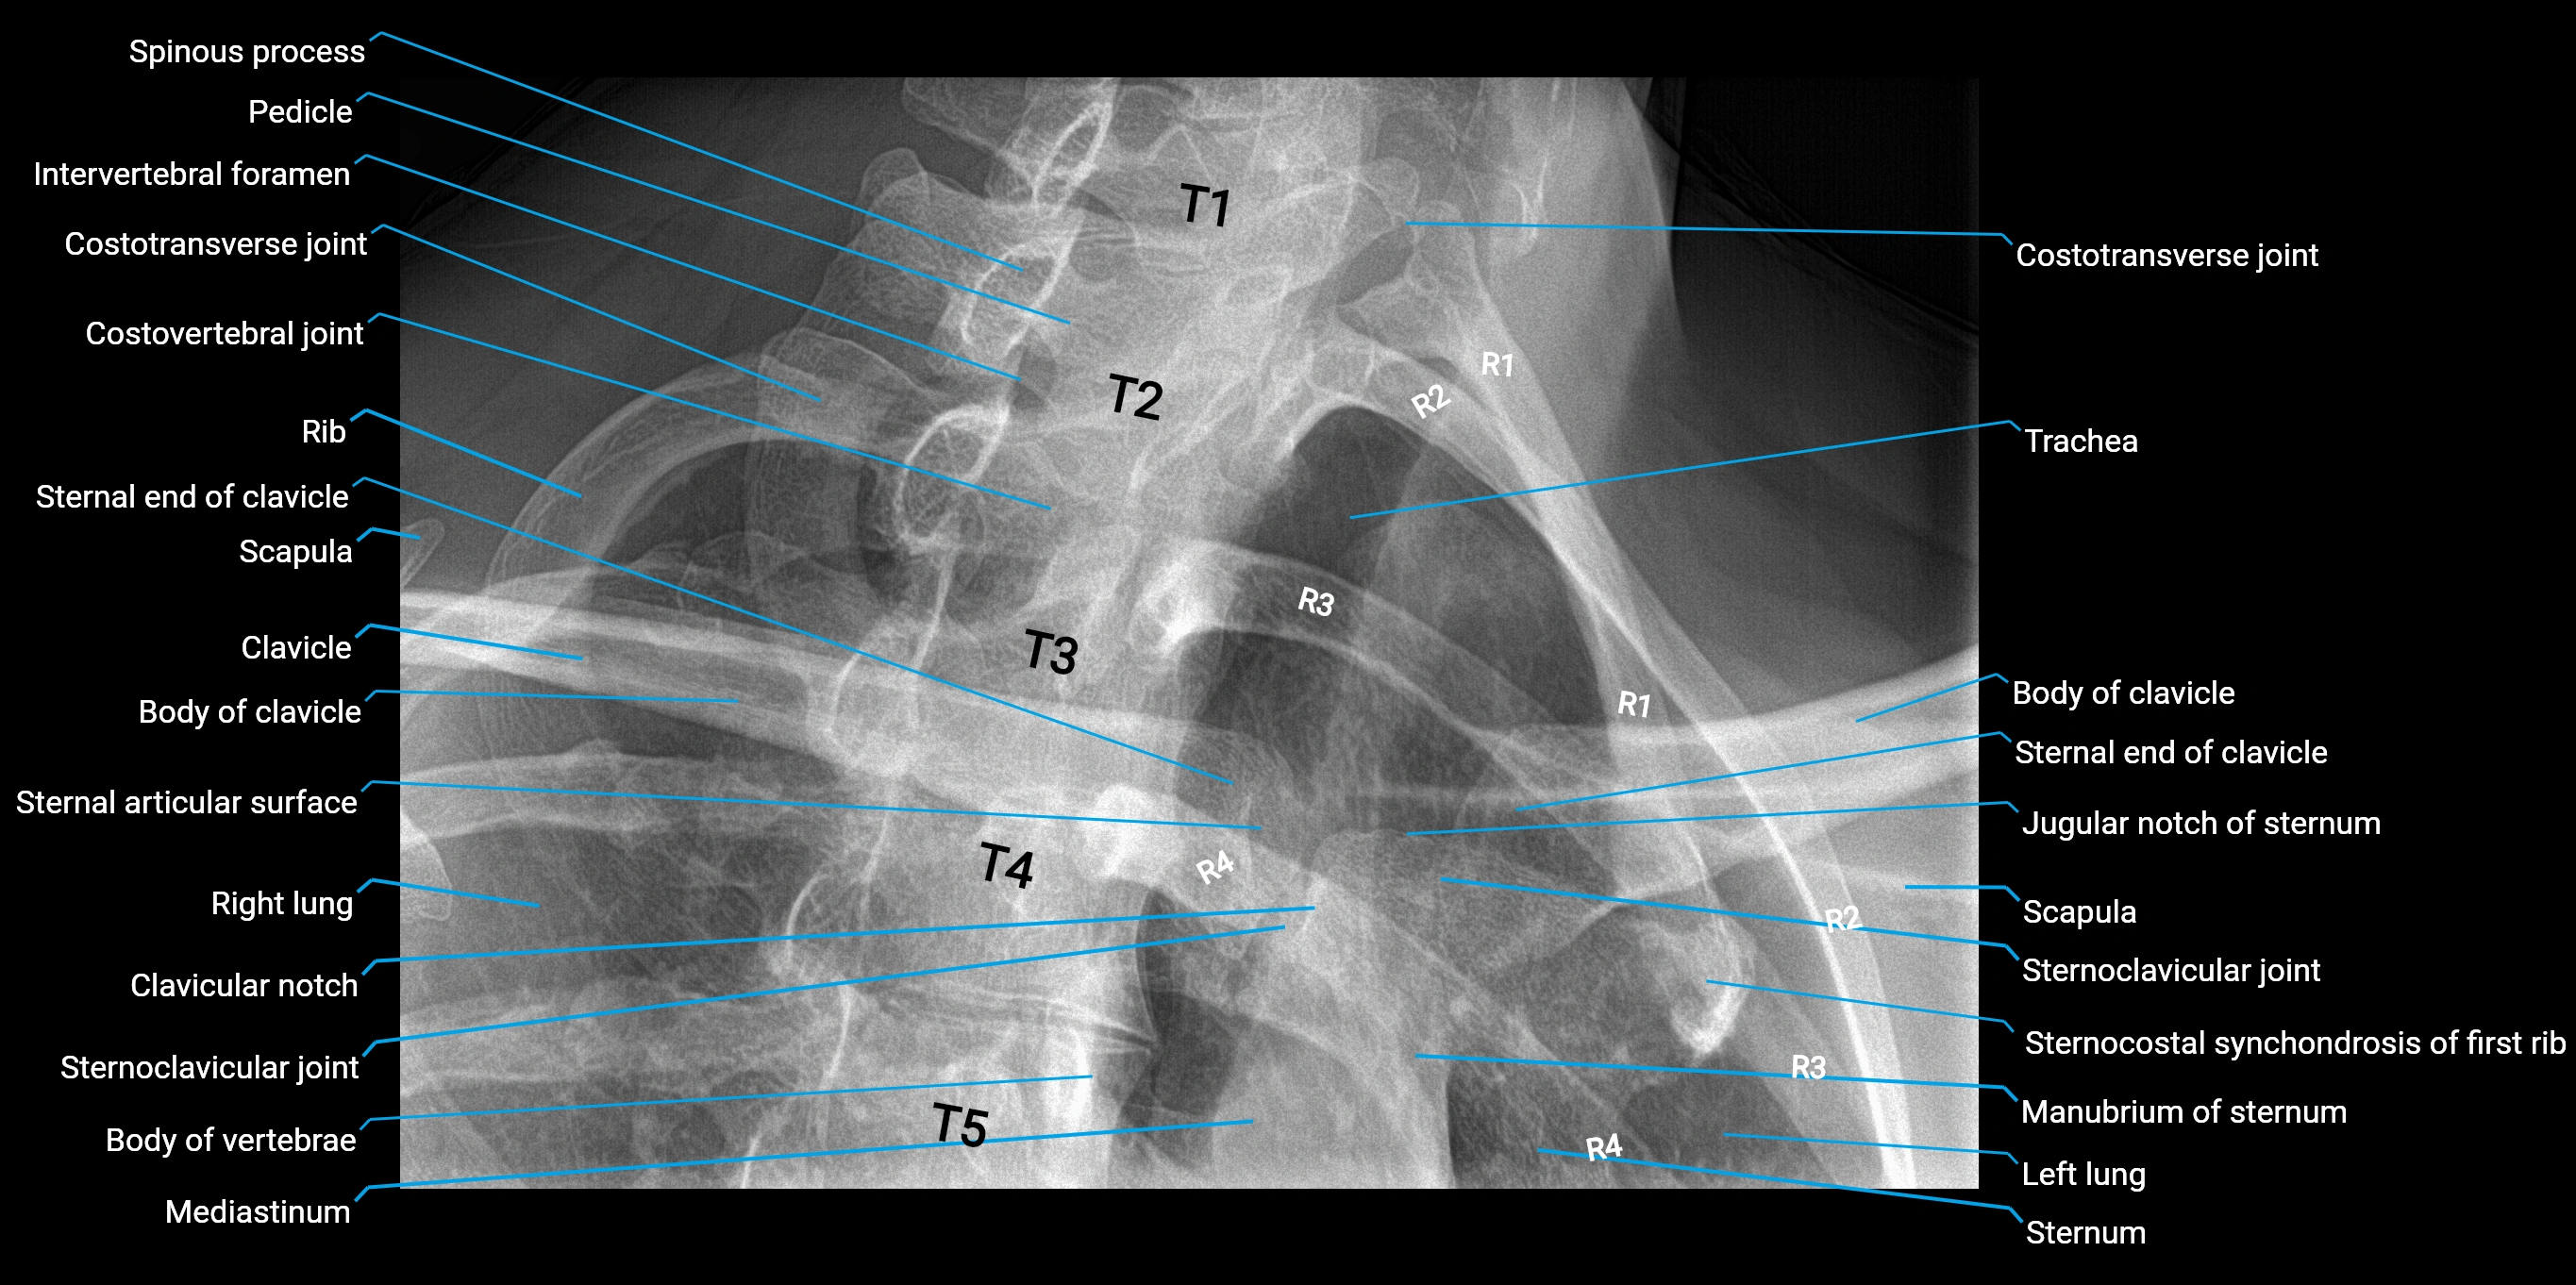

Chest radiograph (PA view):

• Aortic knob: Smooth, rounded convexity along the left upper mediastinal border

• Margins: Well-defined and continuous

• Position: Above the left hilum

• Size and contour: Influenced by patient age, body habitus, and aortic orientation